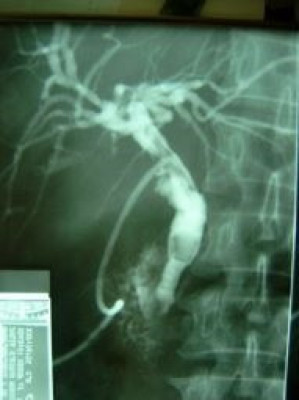

Litotripsia y extracción de cálculo de coledoco residual

Envíado por Dr. Carlos Miguel Zavaleta Consuegra